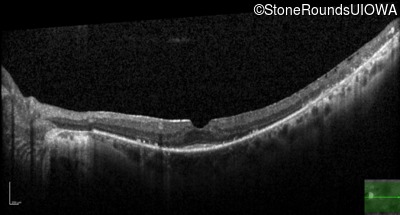

Optical Coherence Tomography - Right - 20/20

Exemplar / OCT Stack

OCT Stack